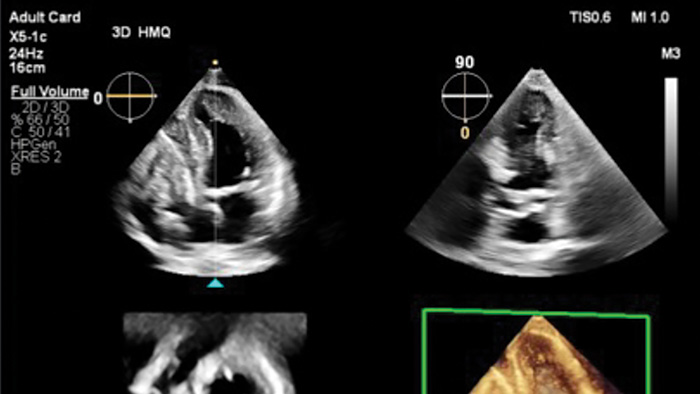

O Transcend Plus melhora visivelmente a nitidez, o contraste e os detalhes em imagens 2D e 3D, apresentando os mais recentes aprimoramentos aprovados pela FDA para EPIQ CVx e Affiniti CVx. Essas atualizações oferecem suporte superior à visualização da anatomia e função cardíacas, permitindo confiança no diagnóstico mesmo nos casos mais complexos ou tecnicamente desafiadores. A atualização também apresenta o novo recurso 2D Auto EF Advanced, expandindo os recursos de IA para imagens de contraste - essenciais para avaliar com precisão a função cardíaca.

A Philips agora oferece 26 aplicativos de IA de ultrassom cardiovascular aprovados pela FDA - o maior número do setor - totalmente integrados ao Transcend Plus para os sistemas EPIQ e Affiniti CVx. Entre os aprimoramentos mais recentes a receber a autorização da FDA 510(k) estão o 2D Auto EF e o 2D Auto EF Advanced. Essas ferramentas avançadas são projetadas para simplificar os fluxos de trabalho clínicos e melhorar a precisão do diagnóstico em uma variedade de ambientes de atendimento, desde o laboratório de ecocardiografia até o hospital e clínicas ambulatoriais, pré-avaliação e acompanhamento de longo prazo. Com esses aplicativos integrados de IA, os médicos podem avaliar os pacientes de forma mais rápida, consistente e confiante em todo o continuum de atendimento.

A avaliação da função ventricular esquerda (VE) é uma das aplicações mais críticas em imagens cardíacas, desempenhando um papel central no diagnóstico e gerenciamento de uma ampla gama de condições cardíacas. O Transcend Plus atende diretamente a essa necessidade, fornecendo resultados rápidos e reprodutíveis que ajudam os cardiologistas a avaliar rápida e definitivamente a função do VE de forma consistente em diferentes pacientes e ao longo do tempo. As ferramentas automatizadas minimizam a variabilidade do operador, garantindo medições mais confiáveis e padronizadas, especialmente vitais em ambientes clínicos de alto volume ou alta pressão. Além disso, o Transcend Plus oferece suporte robusto para imagens com e sem contraste. O recurso 2D Auto EF permite avaliações precisas mesmo quando os agentes de contraste não podem ser usados, como em pacientes com insuficiência renal. Com base nisso, o 2D Auto EF Advanced adiciona recursos de quantificação alimentados por IA para estudos de contraste e sem contraste, ampliando a aplicabilidade clínica e aumentando a confiabilidade da medição em pacientes com baixa qualidade de imagem ou janelas acústicas desafiadoras. Esses recursos se combinam para oferecer uma abordagem mais confiante e eficiente para o atendimento cardíaco.